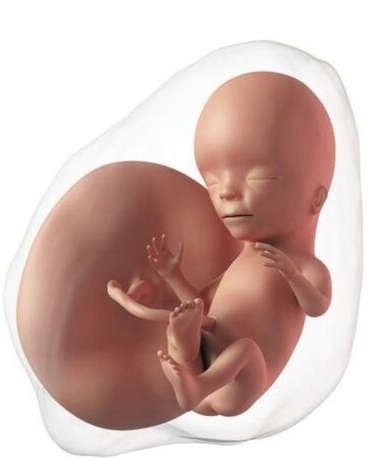

El bebé ahora mide entre 40 a 60 mm. Aunque la cabeza aún es muy grande en relación con el cuerpo, este se va alargando y se va diferenciando la zona de la barbilla y el cuello. El feto empieza a deglutir (tragar) de forma regular y a pasar líquido al sistema digestivo, que está en pleno desarrollo. Excepto el cerebro, la mayoría de órganos están formados "por fuera". Esto quiere decir que su aspecto ya es casi el mismo que tendrán el resto de su vida, pero en su interior todavía sucederán cambios hasta que estén preparados para funcionar fuera de mamá. Los riñones han iniciado ya la producción propia de orina. Esto es necesario para garantizar una adecuada cantidad de líquido amniótico puesto que más adelante la orina será su componente más importante. El líquido cumple un papel fundamental para el bebé; garantiza que el feto está protegido en caso de un golpe accidental a la madre, ayuda a mantener una temperatura estable, impide que el cordón umbilical se comprima, permite el desarrollo pulmonar y del sistema gastrointestinal.

Las náuseas suelen empezar a disminuir a partir de las 11 semanas, pero es probable que el cansancio y el sueño se sigan manteniendo igual que en las semanas previas. Se puede empezar a sentir pesadez en las piernas y calambres.

El útero ya se acerca al borde superior del hueso del pubis, pero todavía no sobresale por encima. En este momento ya ocupa casi toda la pelvis y esto hace que pueda comprimir en ocasiones las venas que devuelven la sangre desde las piernas al corazón. Cada vez va a ser más difícil disimular el embarazo, aunque esto es muy variable.